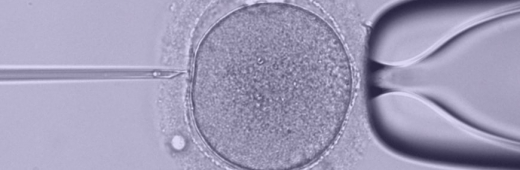

НЕПОСРЕДСТВЕННОЕ ОПЛОДОТВОРЕНИЕ

Это очень важная часть процесса искусственного оплодотворения. Предварительно мужчине следует сдать сперму для процедуры ICSI или для соединения яйцеклетки со сперматозоидом в специальной емкости (на усмотрение эмбриолога). Врачи-эмбриологи внимательно наблюдают за процессом оплодотворения, следят, чтобы не было патологий и сбоев. Оплодотворенные яйцеклетки помещают в специальный раствор и начинается этап культивации эмбрионов, который занимает 3-5 суток, а когда заканчивается – несколько эмбрионов вводят в полость матки. Остальные могут подвергнуть криоконсервации для повторения процесса в случае неудачи.